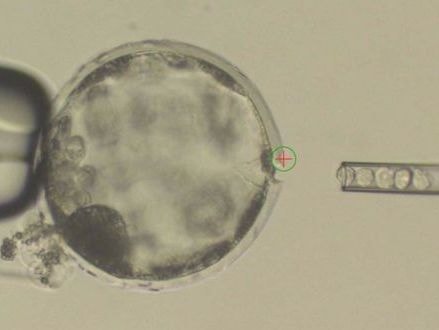

美国制造人猪杂交胚胎

加州科学家将人类细胞植入猪体内,创造出被称为嵌合体的胚胎——猪和人类的杂交后代。